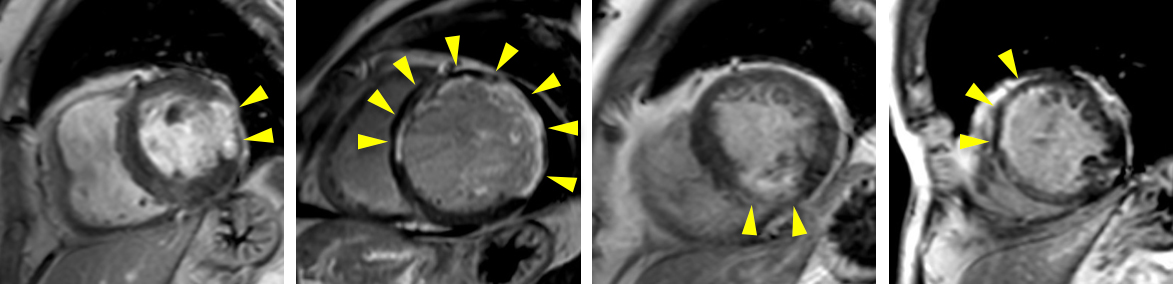

非造影心臓MRI

腎臓の機能が低い場合には、造影剤を用いる冠動脈CT検査は出来ません。MRIでは、造影剤を使用しなくても冠動脈や心臓の機能、心筋の性状を評価する事ができます。

急性心筋梗塞の1例:シネMRI画像(左から中央)では、左心室の一部で収縮が低下している領域があり、心筋の浮腫(T2)画像では、同部位に信号値の高い部分を認め、急性心筋梗塞の所見となります。

造影心臓MRI